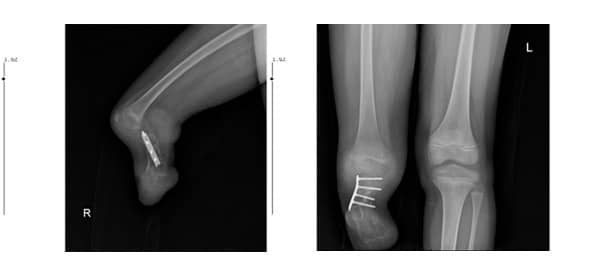

Рентгеновите снимки на пациента показаха пълна агенезия на тибията и фибулата (Фиг. 3 А, В).

Фиг. 3. А: Латерален изглед

B: Антеропостериорен изглед